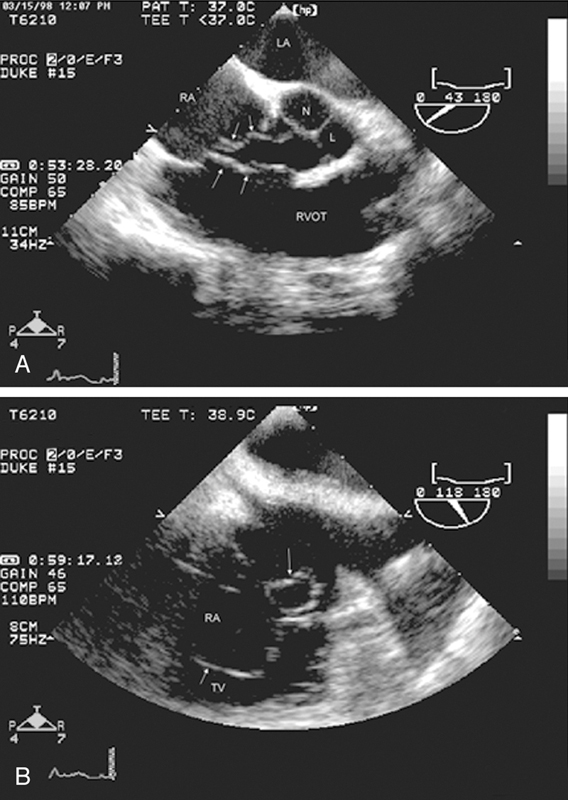

فحوصات تشخيصية لبعض امراض القلب والشرايين التاجية